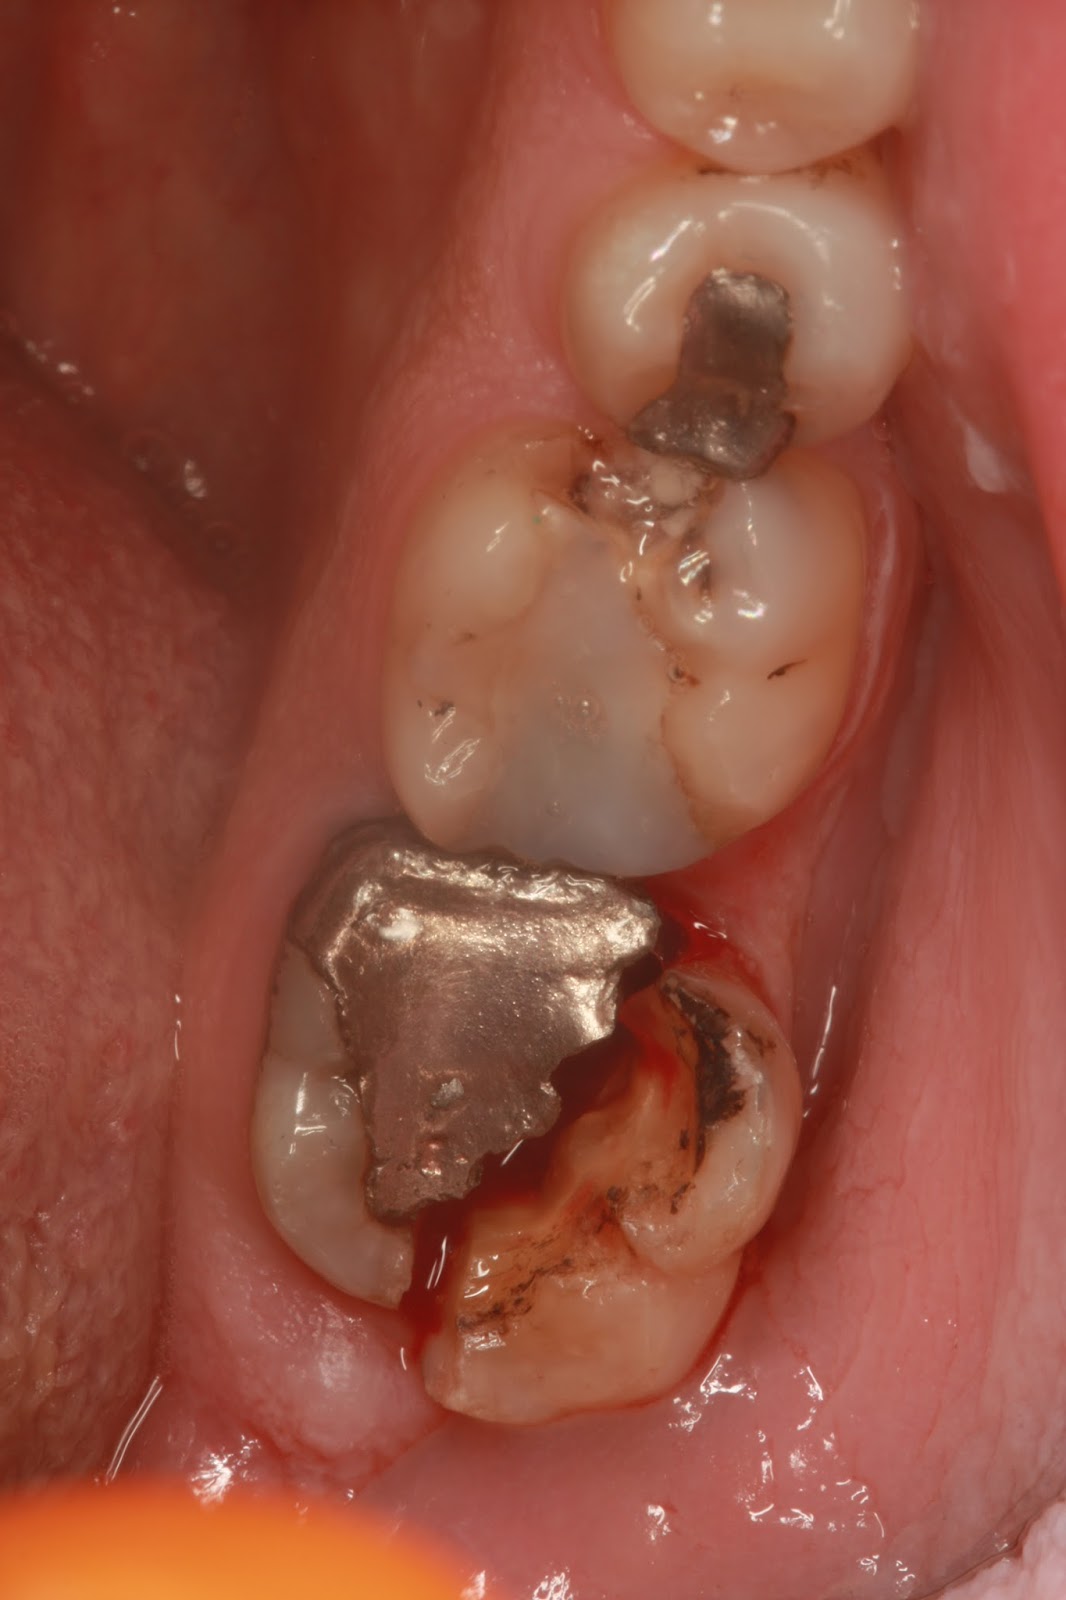

Το ίδιο κάνουμε και στην περίπτωση που έχουμε ένα σφράγισμα,που η τερηδόνα έχει φθάσει κάτω από τα ούλα και δεν μπορούμε να απομονώσουμε για να κάνουμε τις διαδικασίες του σφραγίσματος.Επίσης σε περιπτώσεις κατά τις οποίες έχουμε κάταγμα δοντιού κάτω απο τα ούλα που μπορεί να αποκατασταθεί.

Έχοντας διαγνωσει ακτινογραφικά τη βλάβη κάνουμε τα ακόλουθα :

- Αναισθητοποιούμε τοπικά την περιοχή,για να μην ποναει ο ασθενής

- Κάνουμε έναν κρημνό,κόβουμε χειρουργικά δηλαδή τα ούλα

- Αφαιρουμε κόκαλο,επιμηκύνοντας το δόντι,σεβόμενοι ταυτόχρονα τη μορφολογία της περιοχής.

- Στη συνέχεια ράβουμε τα ούλα και περιμένουμε να ιαθούν,στο νέο επίπεδο,που ορίζει το οστό.

Έτσι τώρα έχουμε τις βλάβες πάνω από τα ούλα,οπότε είναι πιο εύκολα προσπελασιμες και διαχειρίσιμες,αλλά και αρκετό δόντι για να κάνουμε τις επανορθωτικές μας αποκαταστάσεις είτε αυτό λέγεται σφράγισμα,ενδοδοντική θεραπεία και ανασύσταση με άξονα και στεφάνη ή γέφυρα ή οτι άλλο.